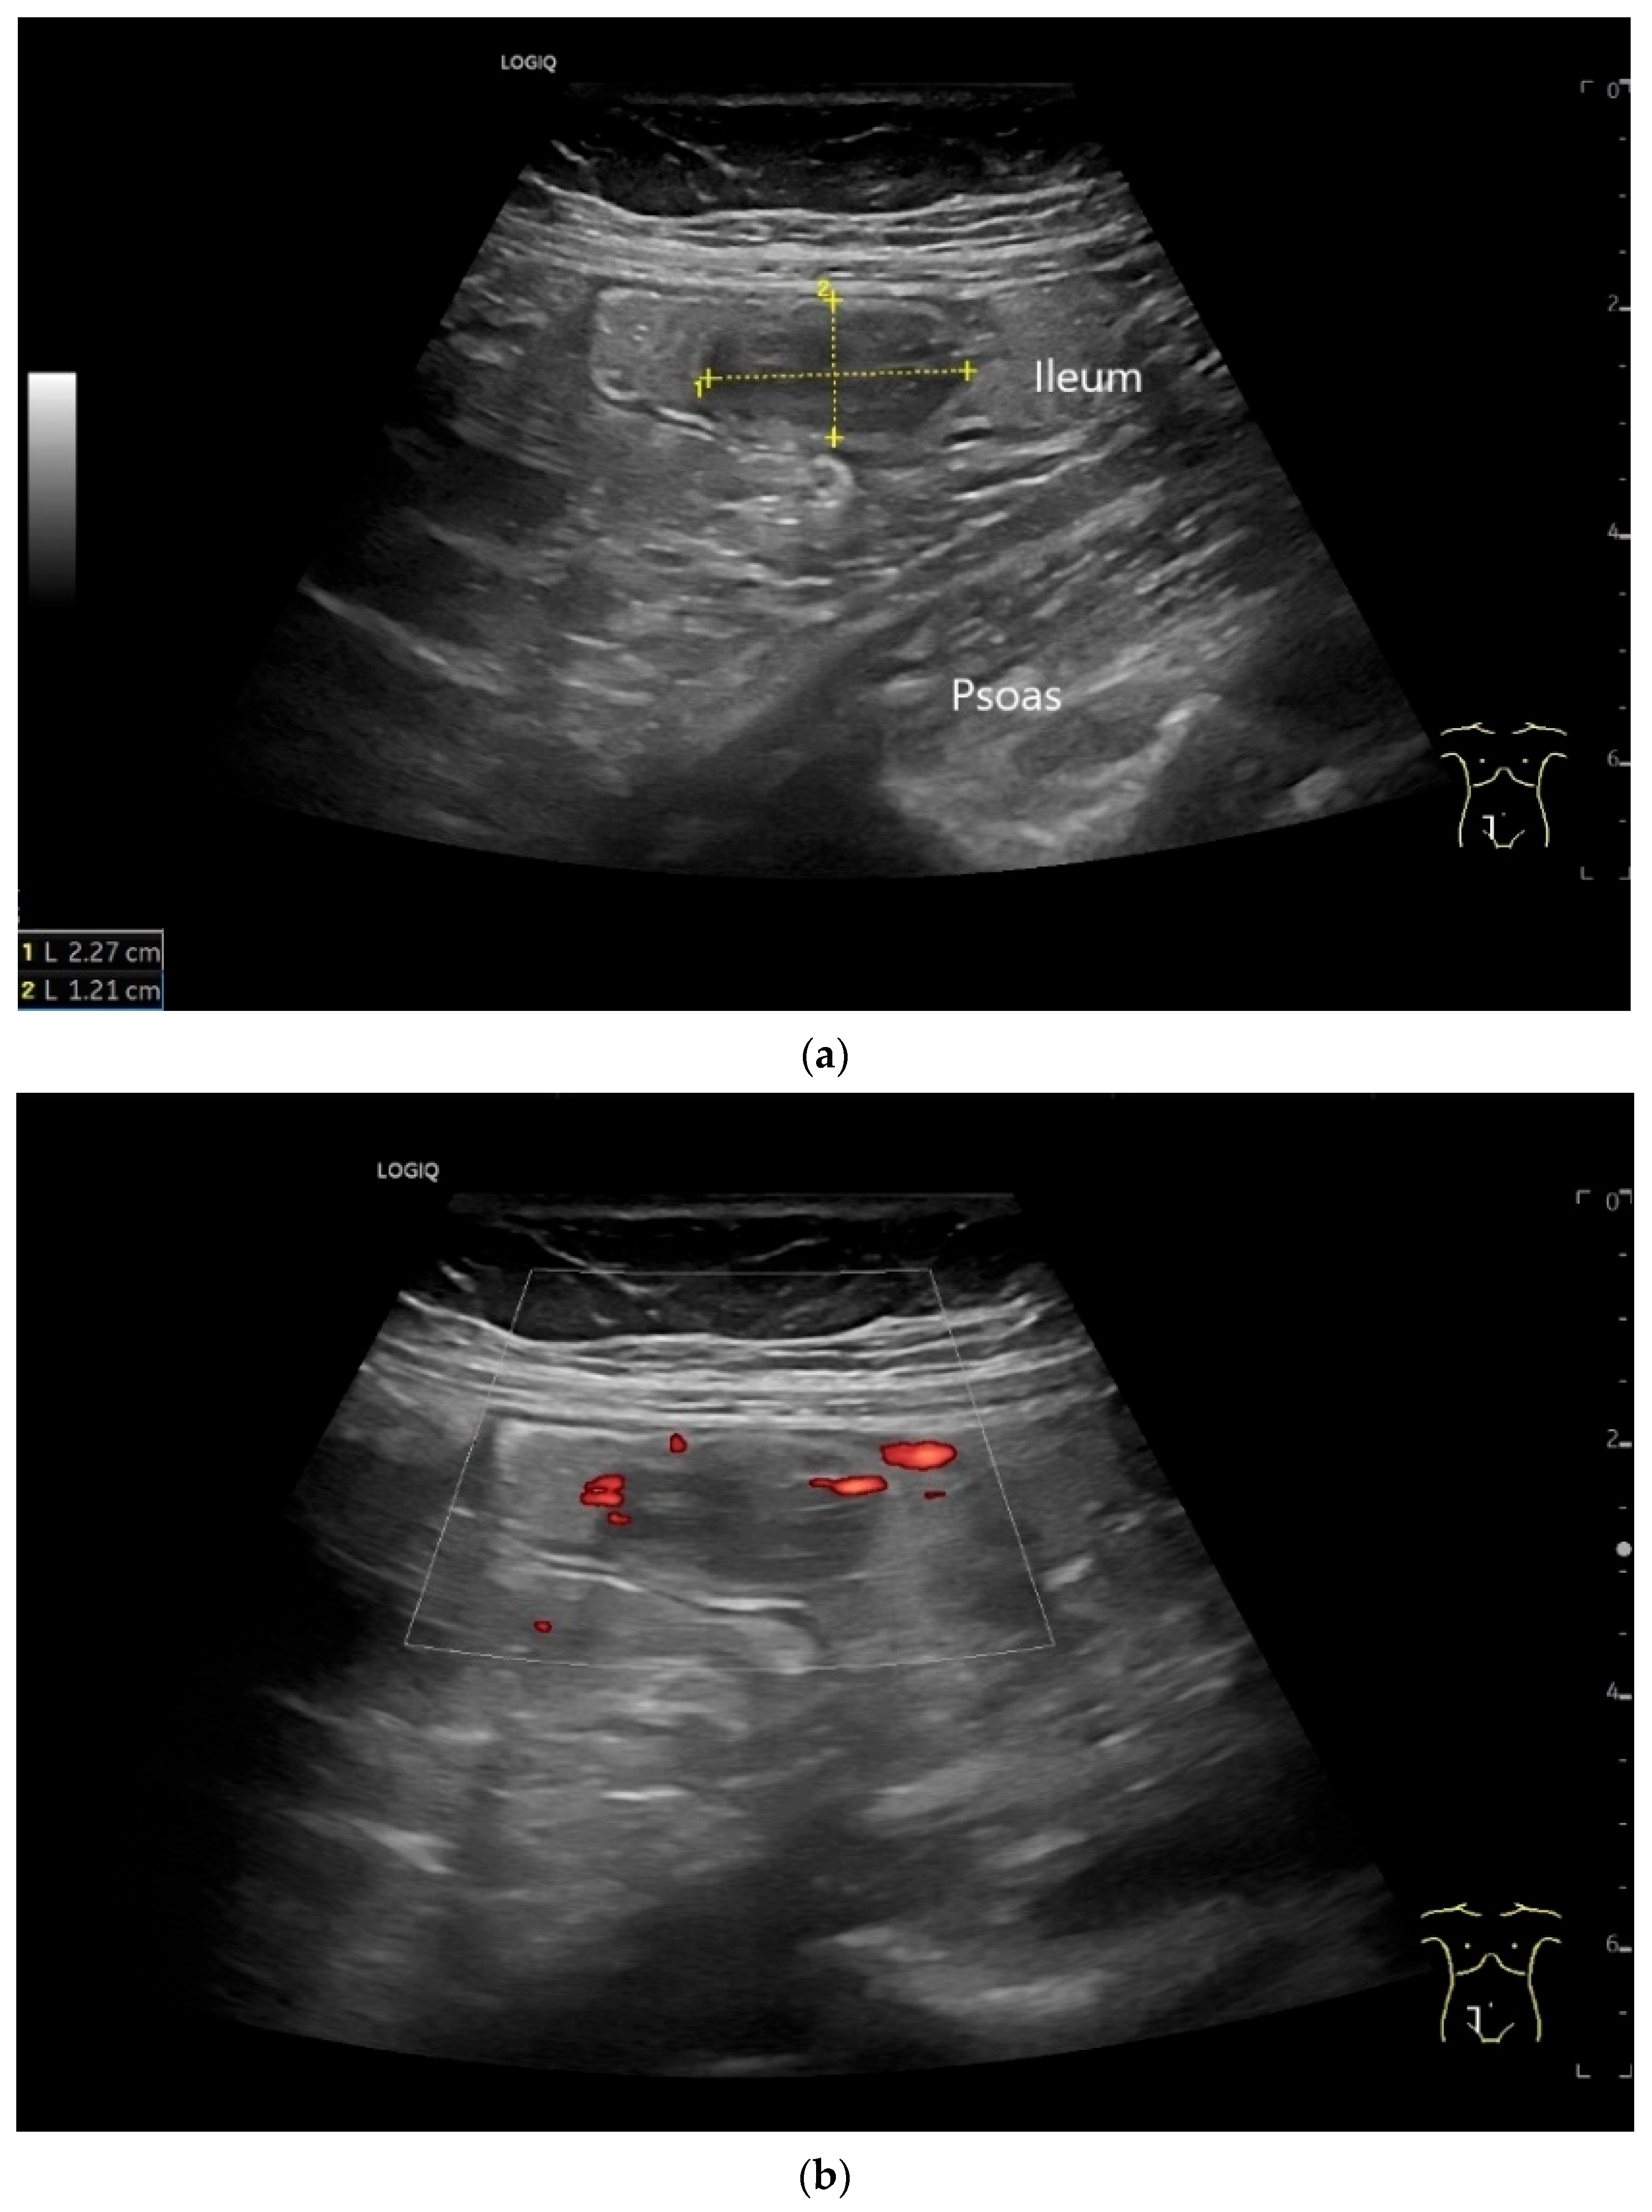

- Grad, S.; Dumitraşcu, D.; Badea, R.; Iobagiu, S.; Pascu, O. Ileal neuroendocrine tumor—Ultrasonographic and capsule endoscopy appearance: A case report. Med. Ultrason. 2010, 12, 245–248. [Google Scholar]

- Schwarze, V.; Marschner, C.; Grosu, S.; Rübenthaler, J.; Knösel, T.; Clevert, D.A. Modern sonographic imaging of abdominal neuroendocrine tumors. Radiologe 2019, 59, 1002–1009. [Google Scholar] [CrossRef] [PubMed]

- Zhao, J.Y.; Zhuang, H.; Luo, Y.; Su, M.G.; Xiong, M.L.; Wu, Y.T. Double contrast-enhanced ultrasonography of a small intestinal neuroendocrine tumor: A case report of a recommendable imaging modality. Precis. Clin. Med. 2020, 3, 147–152. [Google Scholar] [CrossRef]

| Neuroendocrine tumor | Small, nodular hypoechoic wall thickenings, mostly in the submucosa with spreading into the other layers. Usually with small vessels on CDI. Regionally enlarged lymph nodes. Multilocular manifestations are possible. |